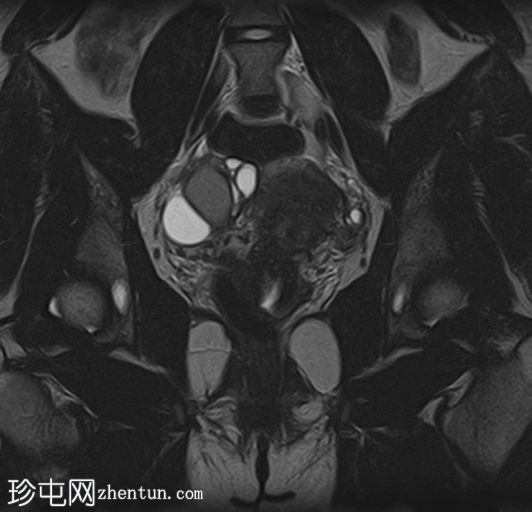

冠状位

T2加权像

在右侧附件区可见一较大病灶,最大轴位和头尾径约为3 x 3.8 x 3.7 cm。该病灶在T1加权像上呈高信号,脂肪抑制像上无信号抑制,在T2加权像上呈低信号(阴影效应)。病灶壁可见T2暗点征结节,增强扫描后未见明显强化。

右侧附件区可见两个较小的类似病灶,最大径约1.2 cm。

双侧卵巢呈多囊性形态,优势卵泡保留。符合多囊卵巢(PCO)的影像学表现,T2加权像呈高信号,T1加权像呈低信号,并可见薄壁强化。